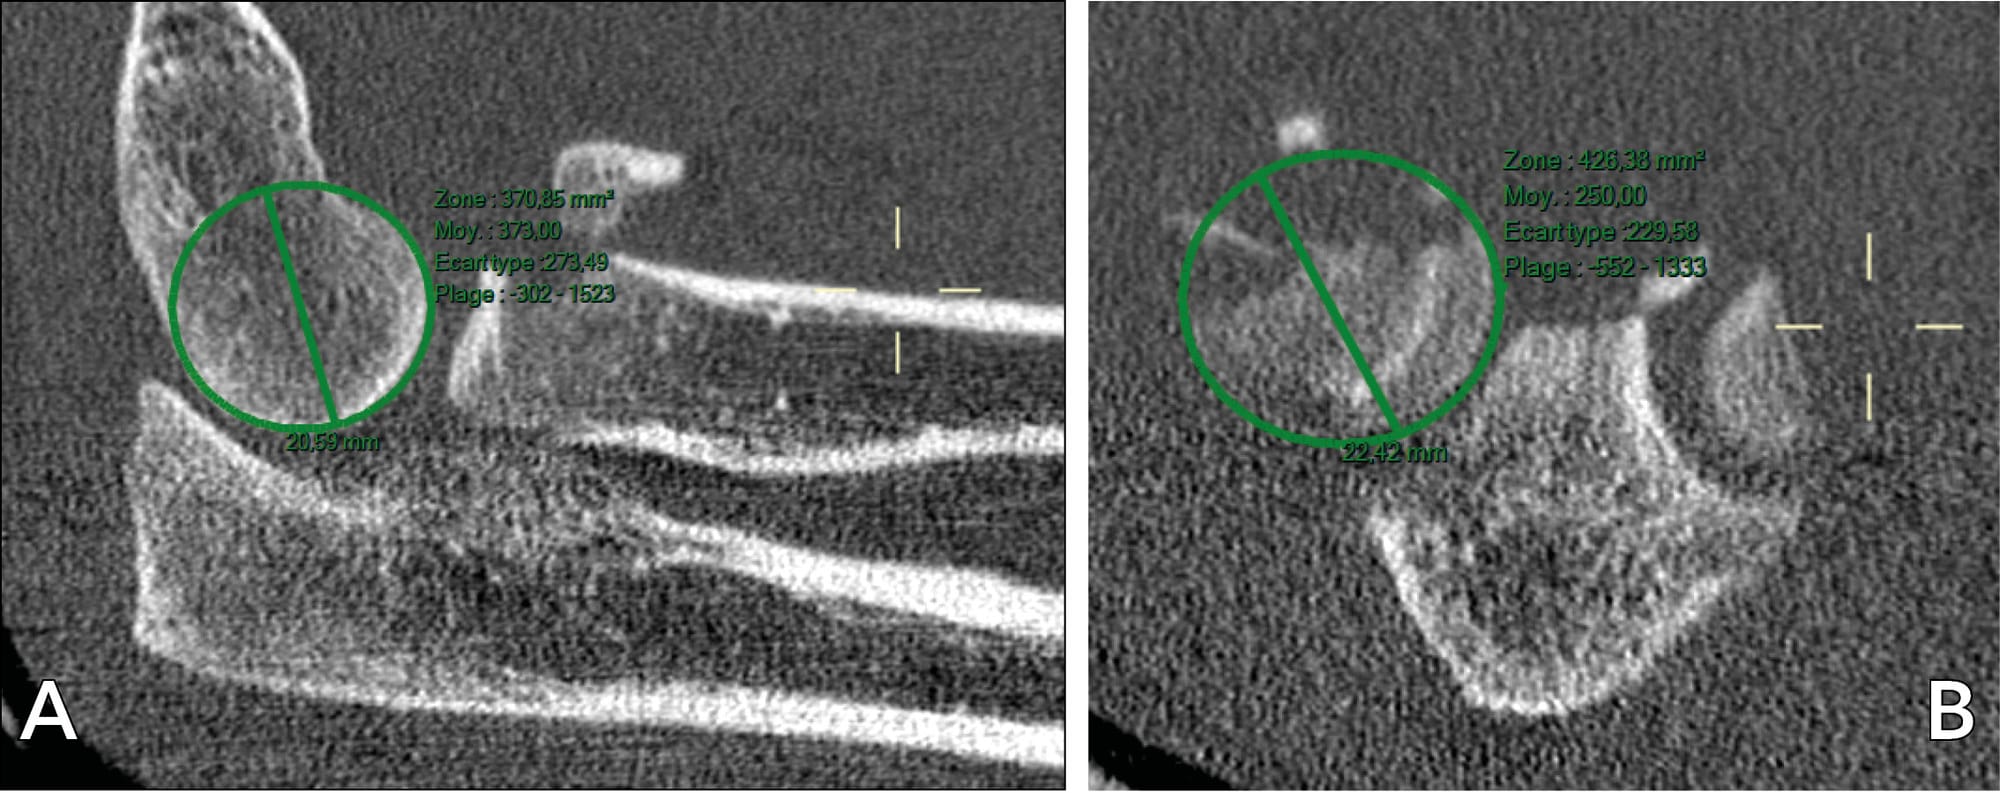

These similarities were also seen in our second case study: the capitellar diameter measured on CT was found to be identical to that of the radial head (figure 8).

Anatomically, the radial head is not a perfect circle but elliptical [7] Captier G, Canovas F, Mercier N, Thomas E, Bonnel F. Biometry of the radial head: Biomechanical implications in pronation and supination. Surg Radiol Anat. 2002;24(5):295–301. . It measures around 24mm at its longest diameter and around 22.5mm at its shortest. It is significantly smaller in women than in men. There is a linear relationship between the minimum and maximum diameters of the radial head, quantified at 1.07, and between the measurement of capitellum and the diameter of the radial head [8] Vaquero-Picado A, Núñez de Armas J, Antuña S, Barco R. Morphometry of the radiocapitellar joint: is humeral condyle diameter a reliable predictor of the size of the radial head prosthesis? J Shoulder Elb Surg [Internet]. 2018;27(6):1092– 6. Available from: https://doi.org/10.1016/j.jse.2018.01.017 .

In an MRI study of 83 patients, Griswold et al. measured the diameters of the radial head and capitellum, finding them to be identical [19] Griswold BG, Steflik MJ, Adams BG, Hebert-Davies J, Tokish JM, Parada SA, Galvin JW. Radius of curvature of the radial head matches the capitellum: a magnetic resonance imaging analysis. JSES Int. 2023 Mar 12;7(4):668-672. doi: 10.1016/j.jseint.2023.02.009.; they concluded that the radial head could be a feasible site for local osteochondral autograft where there is an osteochondral defect of capitellum, with the graft being harvested from the “safe zone” of the peripheral cartilaginous rim of the radial head, which would minimise the morbidity seen with the current practice of harvesting from the knee.